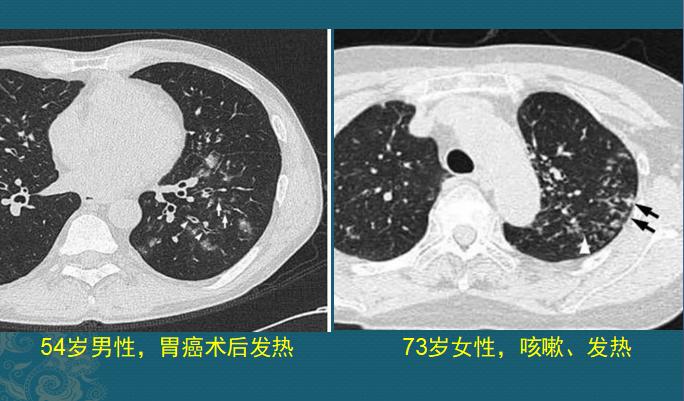

狡猾的金葡菌还有血源性感染

血源性的通常比较重!金葡菌一旦得势,形成局部脓肿大量繁殖,细菌入血,就像野草种子一样,随血液可以到达全身任何部位,常见的有骨髓、关节、大脑、双肺、肾脏等。

如果它们抵达肺部小血管周围生根发芽,就会制造各种毒素引发炎症,表现为多发点片状影或类圆形结节影,边缘清晰或模糊,沿支气管血管束或肺外周和基底部分布,因为是化脓性感染,多数结节最后会坏死、液化,形成空洞,当损伤血管或者形成血管内菌栓堵塞还可以引起远侧肺组织缺血坏死(肺梗死),形成胸膜下楔形肺实变影。

血源性金葡菌肺炎

这些都是金葡菌小草刚发芽,多发小结节、小斑片影,有的形成了小空洞和小气囊,部分与血管关系密切,提示病菌是从血道来源引起肺部播散,及时抗生素治疗可以压制炎症发展。